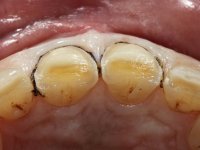

Male patient, 64 years old, non-smoker. Presented widespread dental wear. Both superior and inferior central incisives were lacking enamel on incisal edges, with exposed dentin. Superior central incisives had been previously restored with composite resin, which offered tolerable aesthetics and was prone to frequent fracturing.

It was important to involve the patient in assessing the aesthetic advantage of increasing the height of central superior incisors. For this purpose, a direct mock-up was molded in-mouth, with non-adhesive composite resin. Once the patient agreed to the course of treatment, a silicon matrix was prepared, for subsequent production of provisional veneers. After installing a gingival deflection cord, dental preparation was performed, with special consideration to the fact that the insertion of both veneers would be frontal. Accordingly, mesial and distal walls did not require convergence. The incisal edge was prepared perpendicular to the axis of insertion. After preparation, IDS (immediate dentin sealing) was carried out. A “one-step, double mix technique” was adopted for impression, using putty soft and light silicon. Provisional veneers were produced using dual polymerization composite resin. Color selection was done in the same session.